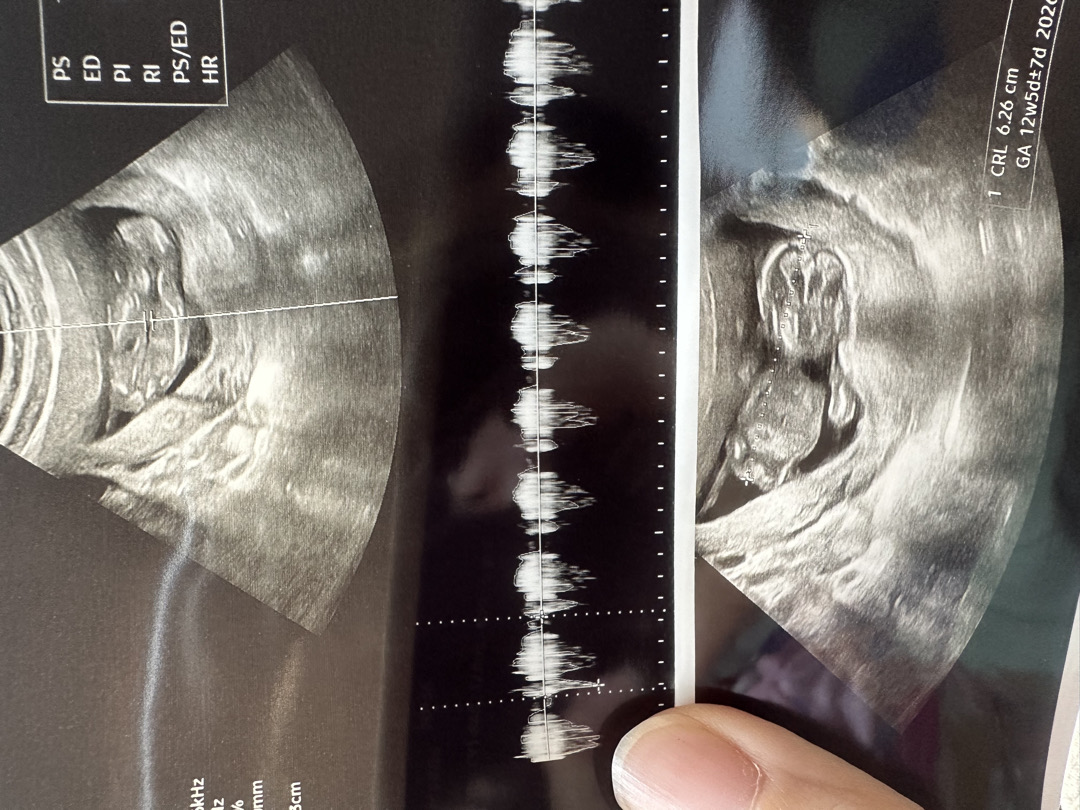

초음파사진이 이상해요…

이제 곧 13주차 접어드는데.. 다른분들은 사진보면 애기 형태가 확연히 보이는데.. 애기가 문제가있는건지 사진이 잘못찍힌건지 걱정되고 너무 속상하네요… 왜그럴까요 ㅜㅜ

자세랑 방향때문이예요ㅎㅎ

저도 11주차에 걱정돼서 서브병원 갔더니 초음파 20초봤나 정말 아기 잘있는지만 확인해주시더라고요ㅜㅜ 그래서 저렇게 흐리고 외계인?처럼 나왔어요 근데 본병원가서 정밀초음파 보니깐 다른분들처럼 선명하고 크게 잘찍혔어요

애기가 엎드려 있으면 저렇게 보여요!! 저희 감귤이도 엎드려있어서 저렇게만 봤어요ㅎㅎ